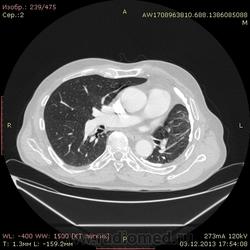

Доброго времени суток уважаемые форумчани! :)Провели исследование КТ грудной клетки с контрастированием, для выявления аневризмы грудного отдела аорты. В результате увидели это:

??? Аневризму честно не вижу (мало опыта в определении аневризм). Тромбоз в бассейне верхней полой вены. В левом легком обызвествленные плевральные шварты? как исход осумкованного плеврита неизвестной давности?

Ребята, вы что, какая жидкость? Чистая известь, посмотрите в костном окне. Отставить натив (в данном случае, хотя для аневризм он обычно нужен). Отставить тромбоз верхней полой вены (потоковые артефакты, не дело вены в артериальную фазу оценивать). Отставить аневризму  аорты, поперчник восходящего отдела на уровне легочного ствола 42мм. А вот легочная гипертензия, здравствуй: поперечник легочного ствола - 37мм, ПЛА - 25мм, ЛЛА - 25мм, НАо - 25-34мм.

Нет ТЭЛА. Фиброторакс слева.

Для справки: холестериновые камни имеют плотность менее 100 ед.Н. Имеющаяся хренотень в левом гемитораксе имеет плотность больше костной, до 1500 ед.Н. Вопрос: какая химико-физико-биологическая реакция может способствовать превращению мягинькаво холестерина в термоядерную плевральную лепёшку?)